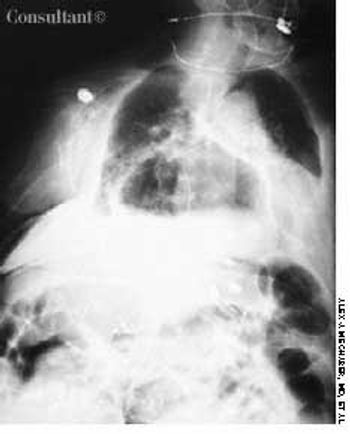

Police brought a delirious, combative 24-year-old man to the emergency department. The patient was unable to provide any history on arrival, but his scarred, blistering lips and his vital signs (blood pressure, 166/102 mm Hg; heart rate, 97 beats per minute; respiratory rate, 24 breaths per minute; and temperature, 38.2°C, or 100.9°F) led to a possible diagnosis of cocaine-induced delirium.